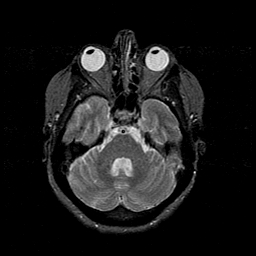

MR Study #1 -- Slice #17